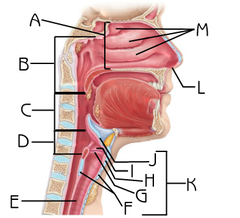

C-Rings (=tracheal cartilage)

Epiglottis

Esophagus

Hard/soft palate

Inferior/middle/superior concha (s.) conchae (pl.)

Internal/external/common carotid artery

Larynx

J

L

Nasal Cavity

Nasal septum

Naso/oro/laryngo-phraynx

Oral Cavity

Paranasal sinuses

G

M

N

Sublingual gland

Submandibular gland

Tongue

D

Trachae

M

Uvula

J

Vestibule (of nasal cavity)

Vocal folds (=vocal cords)